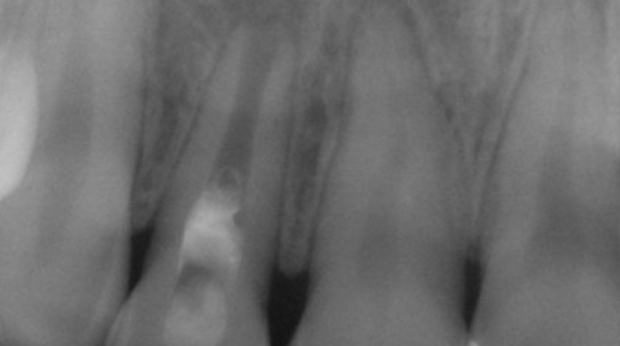

구강외과 진료

매복 사랑니 발치

임플란트와 사랑니 발치는 외과적 시술로 잇몸을 절개하는 외과적 시술은

짧으면 짧을 수록 시술 후 붓기와 통증이 최소화됩니다.

치과의사 경력 14년차 구강외과 전문의가 빠르고 안전하게, 아프지 않게 수술해 드립니다.